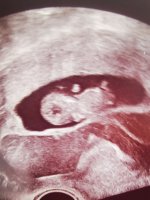

Her er et bilde vi fikk 9+2 (etter mine beregninger mtp eggløsning, 9+4 etter siste mens)Utvendig